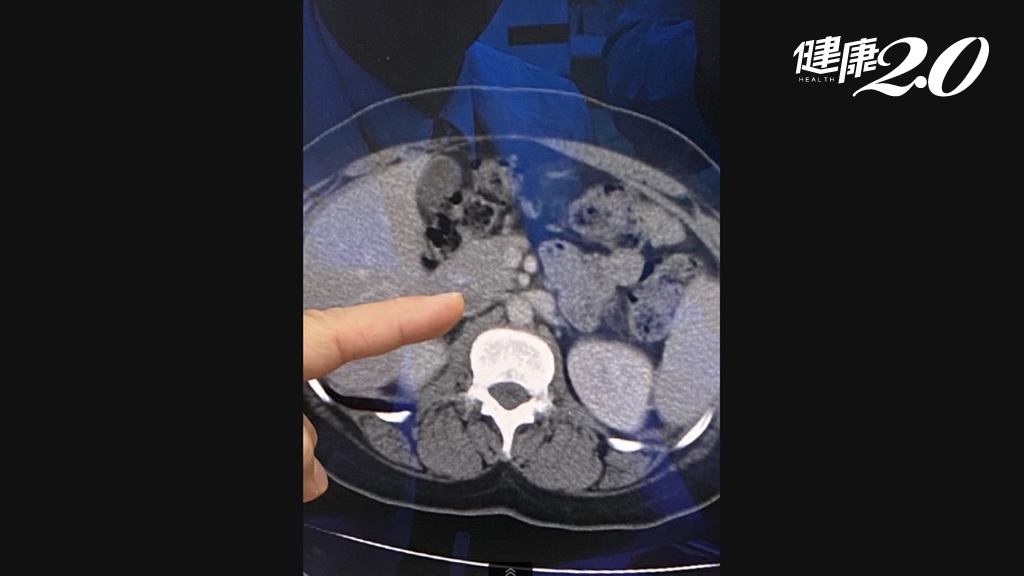

有脂肪肝該怎麼辦?怎樣治療最有效?嘉義大林慈濟醫院肝膽腸胃科醫師周宜群表示,脂肪肝有分酒精性和非酒精性兩種,非酒精性,多是肥胖引起的脂肪肝,最重要的治療方式是飲食控制、減重、運動,來幫助消除脂肪肝。

如果和酒精有關,周宜群說,「戒酒是100%需要」,因為酒精會直接造成肝臟傷害,並且造成脂肪肝,脂肪肝有很大一部分的原因是酒精造成。

周宜群提醒,目前國內病毒性肝炎引起的肝癌雖然還是占最大宗,但是脂肪肝引起的肝癌愈來愈威脅國人健康,尤其是飲酒引起的脂肪肝,已經是國人肝硬化、肝癌的重要原因,提醒大家不要喝酒。